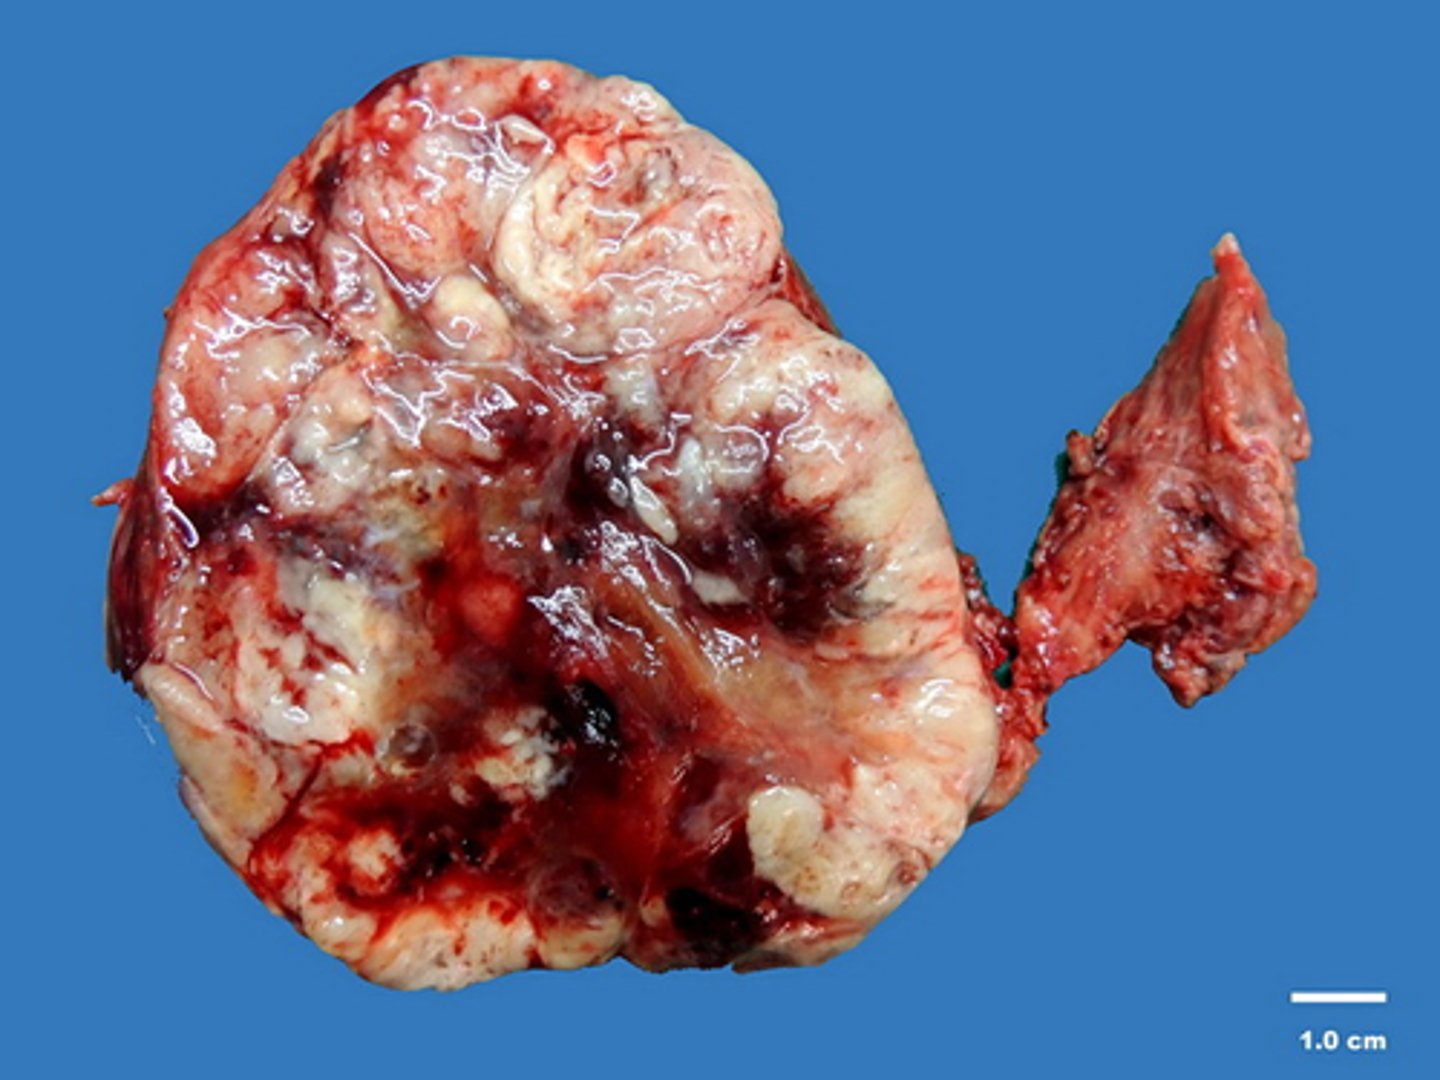

adrenal carcinoma

Pathology?